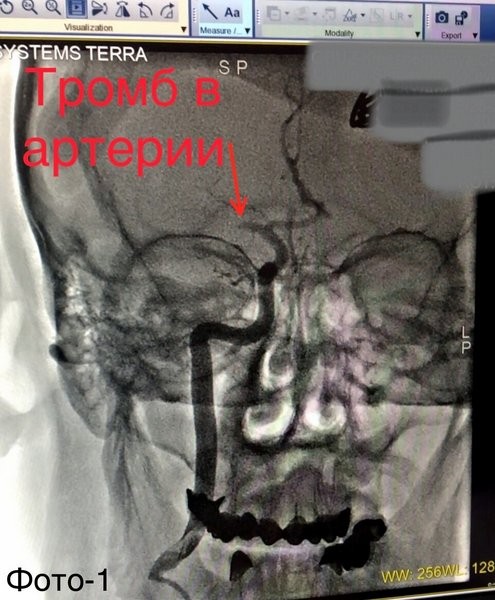

Причиной инсульта послужил «разрыв» атеросклеротической бляшки сонной артерии (фото 2) и, как следствие, тромбоз мозговой артерии (фото 1).

«Пациента взяли в операционную. По данным ангиографии в правой средней мозговой артерии визуализирован тромб (фото 1). Выполнили тромбоаспирацию (удаление тромба) из средней мозговой и стентирование сонной артерии (фото 3) с полным восстановлением кровотока по мозговым артериям (фото 4). Сразу после оперативного вмешательства пациент пришел в сознание. Далее наши специалисты: реаниматологи, неврологи, реабилитологи продолжили бороться за жизнь пациента. 16 дней командной работы позволили спасти его жизнь и восстановить работу мозга», — рассказал Михаил Лапин, заведующий отделением рентгенохирургических методов диагностики и лечения.